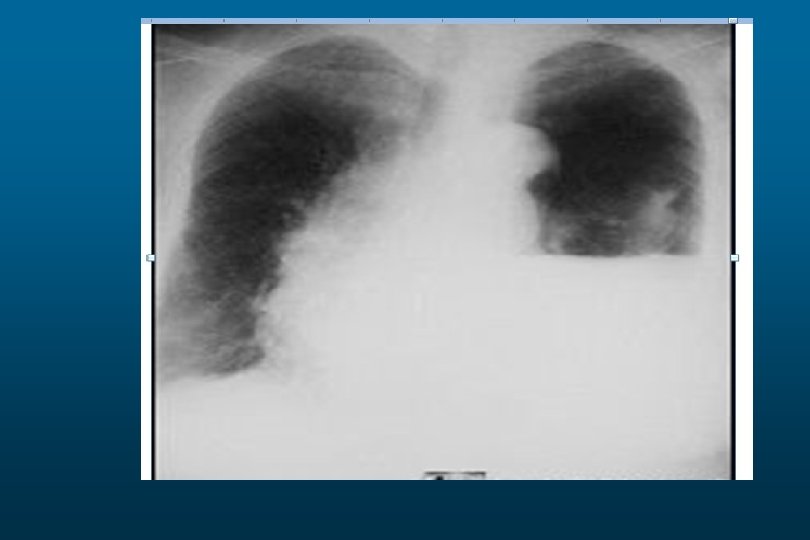

Large pleural effusion

he right hemithorax is opaque There is a shift of the heart and trachea

he right hemithorax is opaque There is a shift of the heart and trachea away from the side ofo pacification This is characteristic of apleural effusion